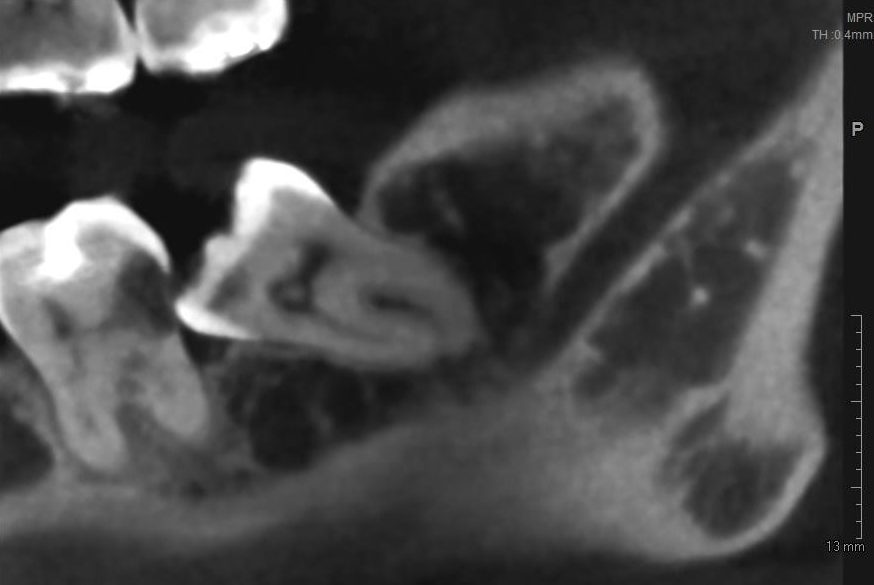

— ортопантомография или, что лучше, конусно-лучевая компьютерная томография. По данным рентгенологического обследования можно определить стадию формирования зуба, направление его движения, отношение к прилежащим структурам, соседним зубам, а также форму и размер образовавшейся под капюшоном полости.

— по данным рентгенодиагностики (КЛКТ или ортопантомограммы) зуб находится в стадии прорезывания (верхушки корней не сформированы), ось прорезывания зуба имеет более-менее правильное направление, его коронковая часть не повреждена кариесом.

— если по данным рентгенологической диагностики причинный зуб имеет сформированную корневую систему, зуб явно уже не прорезывается или, что хуже — упирается коронковой частью в наружную косую линию, соседний зуб или куда-нибудь еще